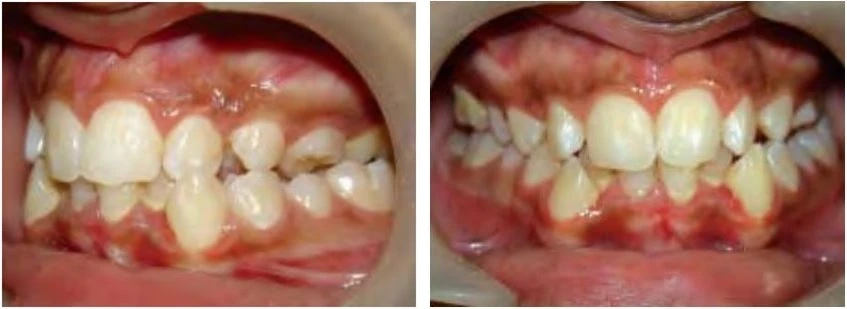

Khớp cắn nằm về phía trước so với bình thường

Với loại này, khi các răng gặp nhau tại khớp cắn trung tâm thì cung răng hàm dưới nằm về phía trước hơn.

Khớp cắn nằm về phía sau so với bình thường

Ở đây, khi các răng gặp nhau tại khớp cắn trung tâm thì cung răng hàm dưới nằm về phía sau hơn.